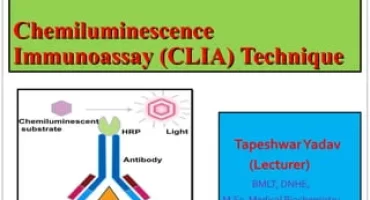

31 March 2023 by admin, in TechnologyCHEMILUMINESCENCE IMMUNOASSAY (CLIA)

Chemiluminescence Immunoassay (CLIA) provides a sensitive, high throughput, full...READ MORE + 31 March 2023 by admin, in Technology